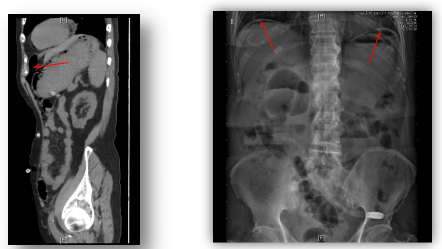

腹腔里的膈下游离气体

北京清华长庚医院肾内科(曹明霞)近期腹膜透析门诊收治一位87岁男性患者,腹膜透析2年,主诉上腹疼痛,腹胀3天”就诊。疼痛位置位于双侧肋下,远离腹透管出口,出口也并无感染迹象,挤压隧道也无分泌物,立位腹平片显示管路位置正常,但是双膈下均有游离气体,膈下气体的位置与疼痛的位置一致,气体从哪儿来的呢?是因为腹透误操作?还是有腹腔感染?肠穿孔?腹透液常规检查未见白细胞,腹腔CT也未见肠穿孔,提示气体是因腹膜透析操作进入的,经多次排气治疗后患者症状好转。